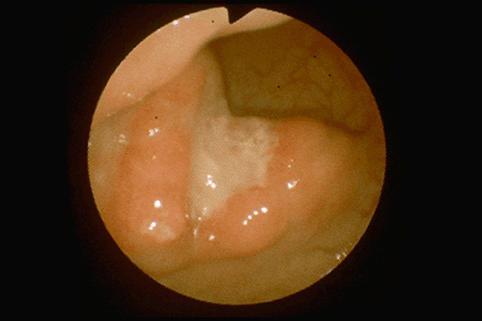

Colitis cystica profunda located mainly in the anterior wall of the rectum.

Tumor-like lesions/Colitis cystica profunda

Large intestine(Colon)/Rectum

Endoscopy

35 - 40